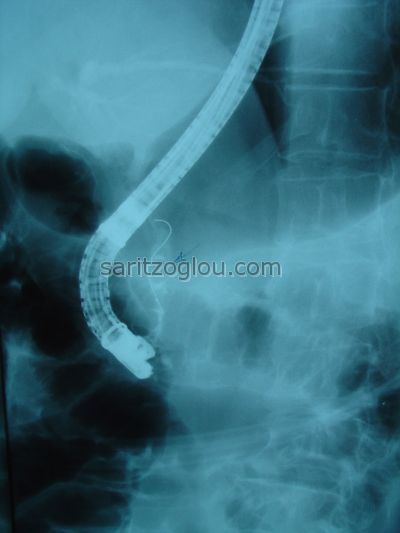

Η σκιαγράφηση του χοληδόχου πόρου καταδεικνύει την παρουσία λίθου εντός του χοληδόχου πόρου (βλέπε βέλος)

Παρουσία λίθου εντός του χοληδόχου πόρου. (βλέπε βέλος)